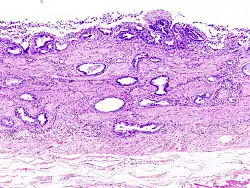

- Gallbladder adenocarcinoma lymphatic invasion histopathology

- Gallbladder adenocarcinoma histopathology

- Gallbladder carcinoma